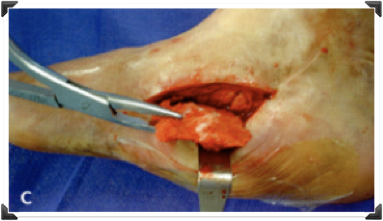

Foto Clínica

Post Inmediato